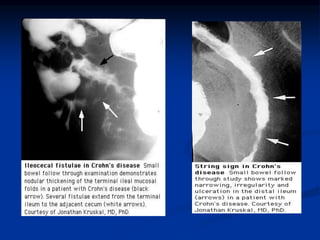

Radiologic features of CD and UC

UC

CD

Feature

Collar button

ulcers

Nodularity

granularity

cobble stoning

string sign of SB